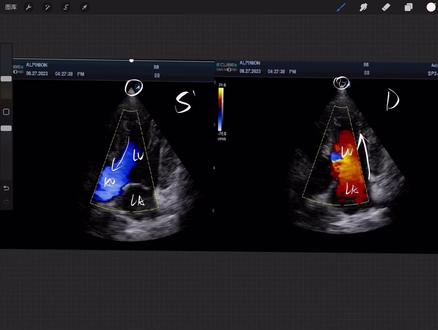

今天给大家分享一下关于多 pro 混叠血流方向层流团流,那我们可以看到这是一个二维的图像,当我们使用彩色多 pro 的时候,就可以将血流通过颜色展现出来, 那我们可以看到远离探头的血流,也可以看到走向探头的血流。要想识别到底是远离和走向,第一是根据原色,第二是根据解剖的位置, 我们可以看到走向探头的红色血流,当然是从新房到新史的, 那我们也可以看到远离探头的血流,比如从新时到主动脉的,所以说解剖位置我们一定要搞明白,我们发现血流的啊颜色, 当这个血流啊,他的越颜色越亮的时候,我们提示越快,当他的颜色越暗的时候,我们就提示越慢,所以说识别这个正常的血层流的血流,我们一一定要非常的注意啊,也是要非常谨慎, 走向探头的红色血流和远离探头的蓝色血流,那在调节过程中我们会有很多设置,当你的设置啊调整的不对的时候,就会出现一些啊假的这种现象,比如混叠现象, 当然我们先给大家看一些啊,比较这个正常的啊,就是比较典型的一些病例,那可以看到这是一个事间隔缺损的病例, 包括他出现了一个继发性的肺动脉狭窄,那我们看到啊,从左心到右心的分流,我们看到了一个高速的血流,此时我们的尼奎斯的底线包括标识调的还是比较高,那么仍然是看到了一个啊这种团流的这种信号, 所以说呢,这种呢是一个啊比较真实的团流,主要是由视间隔缺损导致的, 那我们再看一下,当你的标识设置过低的时候,可能就会导致啊, 本身啊,是不是团就是本身它是一个健康的一个血流,但你在颜色上面也仍然看到了这种啊五彩样,或者是啊花样的花死五彩蒸的啊这种混叠效应。所以说啊,我们在日常过程中判断到底是 流还是团流,判断是正常的血流还是异常的,我们是一定要将自己的这个机器设置要调的比较好,那接下来我们花一点点时间为大家这个详细的讲解,关于这个呃层流团流,包括这个啊混碟效应和调整。 好,那我们给大家讲一下。首先我们先讲一下正常的, 那我们要了解血流方向,在之前我们已经讲过原理了,这边是 l a, 这边是 lv, 那这边是 a o, 这个是探头的方向, 那在收缩器的时候我们就可以看到啊,远离探头的血流,也就是从这个左使到主动脉的血流,那远离探头我们就会发现他是一个蓝色, 那在舒张期的时候啊,因为我们的这个防止半打开动脉半关闭,这个时候左防就会往左使流动,这个时候我们就发现就有一个走向探头的血流了,对吧?走向探头的血流, 那这个颜色是没问题的,可是有的时候总是会因为我们人为的因素导致正常的,也会当异常的判断。好,那当我们的这个啊标尺 的太低的时候啊,标尺太低的时候,比如我们现在可以看到这个是七十六,比如当我们标尺非常低的时候就可能会出现这种啊,我们所称的这种混叠效应 啊,混叠效应,什么叫混叠效应?当标值非常低的时候,就可能导致我们无法判断血流 油的一个方向了啊,他就会出现一些五彩样的信号啊,五彩样的信号, 比如我们看一下这个, 那么可以看到这个标尺啊,我们只设到了二十七点六,那我们就看到了他出现了这种,对吧?五彩样的这种, 实际上他就是出出现好像像川流,对吧?啊?好像川流,但他实际上只是一个混叠的 啊,多 pro, 只是我们没有设置好人为的因素,对吧?啊啊,人为的因素,一定要将标尺调高一点,那么到底会建议多大的这个标尺 啊?标尺也好啊, p r f 也好,比如我们的脉冲宠物频率,对吧?脉冲宠物频率, 那实际上都是啊,一样的,这个时候呢我们就会建议把它提高,比如提到这个啊,六以上,对吧?六以上,当你提到六以上的时候,我们的速度啊也是比较高的,对,我们的速度也是比较高的速度, 那实际上这个我们的这个速度标尺也就是这个速度的一个范围啊,速度的范围,当这个当你的这个速度范围设置的小于他真实的流速的时候,他就会出现这种混叠效应, 如果你的这个啊设置是没问题的,比如你的标尺设置的没问题,他还是出现了这种这个啊就是混叠效应,或者是啊,我们又被称为可能是不是有屯留了, 或者是不是狭窄了,那我们啊一定要去观察二维啊,观察二维看看是不是有一些啊狭窄啊,反流 啊,或者是不是啊有分流?对,或者是不是有分流。那同时我们也要啊,做一下关于这个其他的多 pro, 对吧?其他的多 pro, 那我们做哪个呢?哦,主要就是 频谱啊,频谱,比如我们的 c w 去评估一下。呃,流速,当流速非常高的时候,我们就考虑他是不是啊出现了这个 啊狭窄,或者是写反流,或者是些分流。所以说啊,在日常过程中我们一定要注意自己的标尺啊, 不要太低啊,不要太低。好,那我们今天的课程就分享结束。